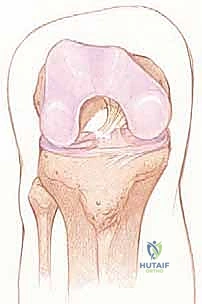

يقع الرباط الصليبي الأمامي في قلب مفصل الركبة، ويمتد بشكل مائل من الشق بين اللقمتين (Intercondylar notch) في عظم الفخذ، نزولاً إلى السطح العلوي لعظم الظنبوب (القصبة).

من الناحية الوظيفية والتشريحية، لا يعمل الرباط كوحدة واحدة، بل ينقسم إلى حزمتين رئيسيتين تعملان بتناغم عجيب:

1. الحزمة الأمامية الإنسية (Anteromedial Bundle - AM): هذه الحزمة تكون مشدودة بشكل رئيسي عندما تكون الركبة في وضعية الانثناء (Flexion). وظيفتها الأساسية هي منع عظم القصبة من الانزلاق للأمام بعيداً عن عظم الفخذ.

2. الحزمة الخلفية الوحشية (Posterolateral Bundle - PL): تكون هذه الحزمة مشدودة عندما تكون الركبة في وضعية الاستقامة الكاملة (Extension). هذه الحزمة هي المسؤولة الأولى عن توفير الثبات الدوراني للركبة، وهي التي تمنع الركبة من الالتواء أثناء تغيير الاتجاه المفاجئ.